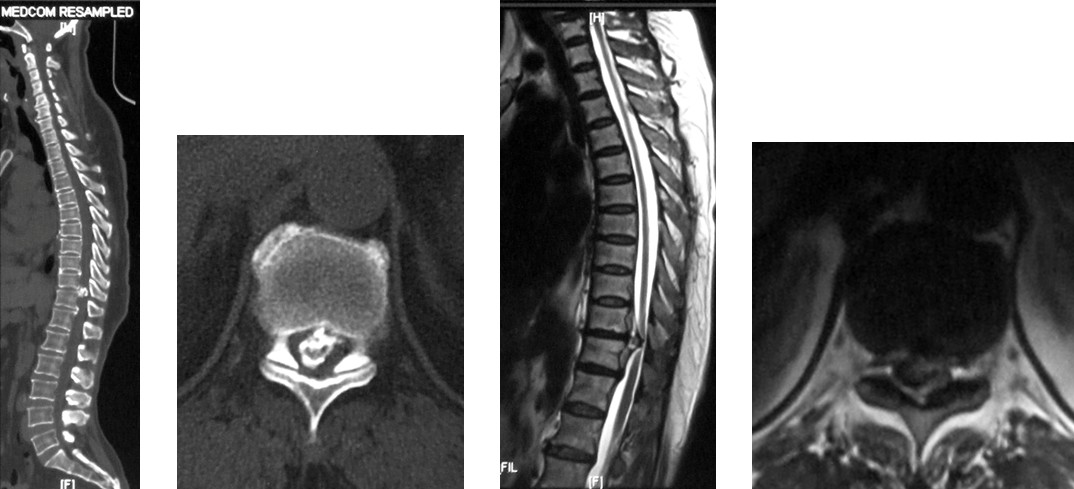

4. 典型病例:病例1,患者男性,40岁,司机。主因胸腰背部疼痛3年,肛周麻木、性功能减退并伴双足下垂2年,症状加重且二便肥力、无法工作1年入院。入院查体:一般情况良好,体胖、体重105kg。步态不稳,步行缓慢。胸腰段脊柱背部轻压痛,无放射。双侧股四头肌力IV级,双侧胫前肌力I级,双侧足下垂。鞍区感觉减退,无病理征。双侧跟、膝腱反射消失。血化验检查正常。X线平片显示T12~L1椎间隙明显变窄。CT显示T12~L1椎间盘突出并椎体后缘离断。MRI显示T12~L1椎间盘呈中央型突出,椎管狭窄,脊髓明显受压变形。入院诊断:T12~L1椎间盘突出症伴椎体后缘离断,马尾神经损害。术前检查完成后,在气管插管全麻下行上述经极外侧入路T12~L1椎间盘切除手术治疗,整个手术过程顺利,无术中及术后并发症发生,术后1周顺利出院。出院时,其双侧股四头肌、胫前肌肌力已分别恢复至V级和III级;鞍区感觉减退亦有明显好转。术后显示T12~L1突出之椎间盘及离断之椎体后缘已被完全切除,椎间融合器及椎弓根螺钉位置佳,脊柱局部生理曲度良好(图2a~2l)。病例2,女性患者,59岁。主因间歇性跛行,双下肢无力3年入院。入院诊断:T11椎体后上缘骨软骨瘤。以与病例1相同的术式行椎体骨软骨瘤的彻底切除(图3a~3l),无手术并发症发生,术后患者下肢症状明显改善。

图3a~3d. 典型病例2患者术前均显示为T11椎体后上缘骨软骨瘤,分明显突入椎管, 脊髓明显受压.

图3e~3h.典型病历2术中椎管后壁切除及极外侧显露情况

图3i~3l. 典型病例2患者术后之线片, CT, MRI显示骨软骨瘤已被彻底切除, 脊髓获得充分减压, 内固定位置良好.